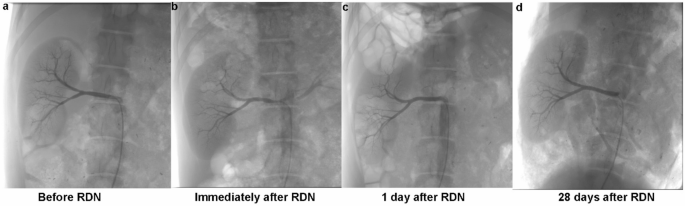

Renal artery angiography(Fig. 4)

Renal artery angiography at different time points (10 W, 10s). (a) Renal angiography before RDN. (b) Immediately after RDN, showing the status of the renal artery. (c) One day after RDN, illustrating the post-procedure vascular condition. (d) Twenty-eight days after RDN, demonstrating the long-term vascular integrity.

Immediately after the RDN procedure, renal artery spasms were observed in all animals. Renal artery angiography performed 1 day post-ablation confirmed that the renal arteries were patent, with no significant stenosis, thrombosis or dissection. The vessels showed normal blood flow, indicating that the procedure did not result in any lasting structural impairment. At the 28-day follow-up, angiography conducted in the 6 experimental animals also showed no significant narrowing or other abnormalities in the renal arteries, further supporting the long-term safety of the laparoscopic RDN procedure in preserving vascular integrity.